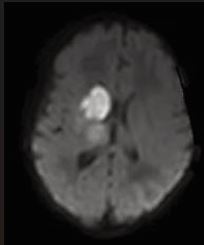

The presence of abnormal neurologic symptoms in the examined 79 infants was observed at the following ages: 9 in the delivery room; 21 during the first 24 hours; 15 during the first or second day of life; 13 at the first or second week; 21 infants showed their first symptoms during the 3rd or 4th month. Examining the Apgar score, 31 out of 79 infants had 9/10 or 10/10, 20 had 8/9 or 9/9, and 28 had an extremely low as 0/0/4 up to 6/7.In 25 patients no abnormal neurological signs were observed during the whole study, including the follow up. Seizures were observed in 50 infants as their first sign (Figure 2), but 8 also had apnea, irritability, and opisthotonic spasms. Neurosonography was performed in all infants, MRI [10], in 77 infants, CAT scan in 1, and no MRI/CAT in 1. Figures 3a, 3b, and 4 show some examples of the lesions.

Figure 3a MCA stroke on the left (a) and right side (b)

https://www.jscimedcentral.com/public/assets/images/uploads/image-1762766148-1.JPG